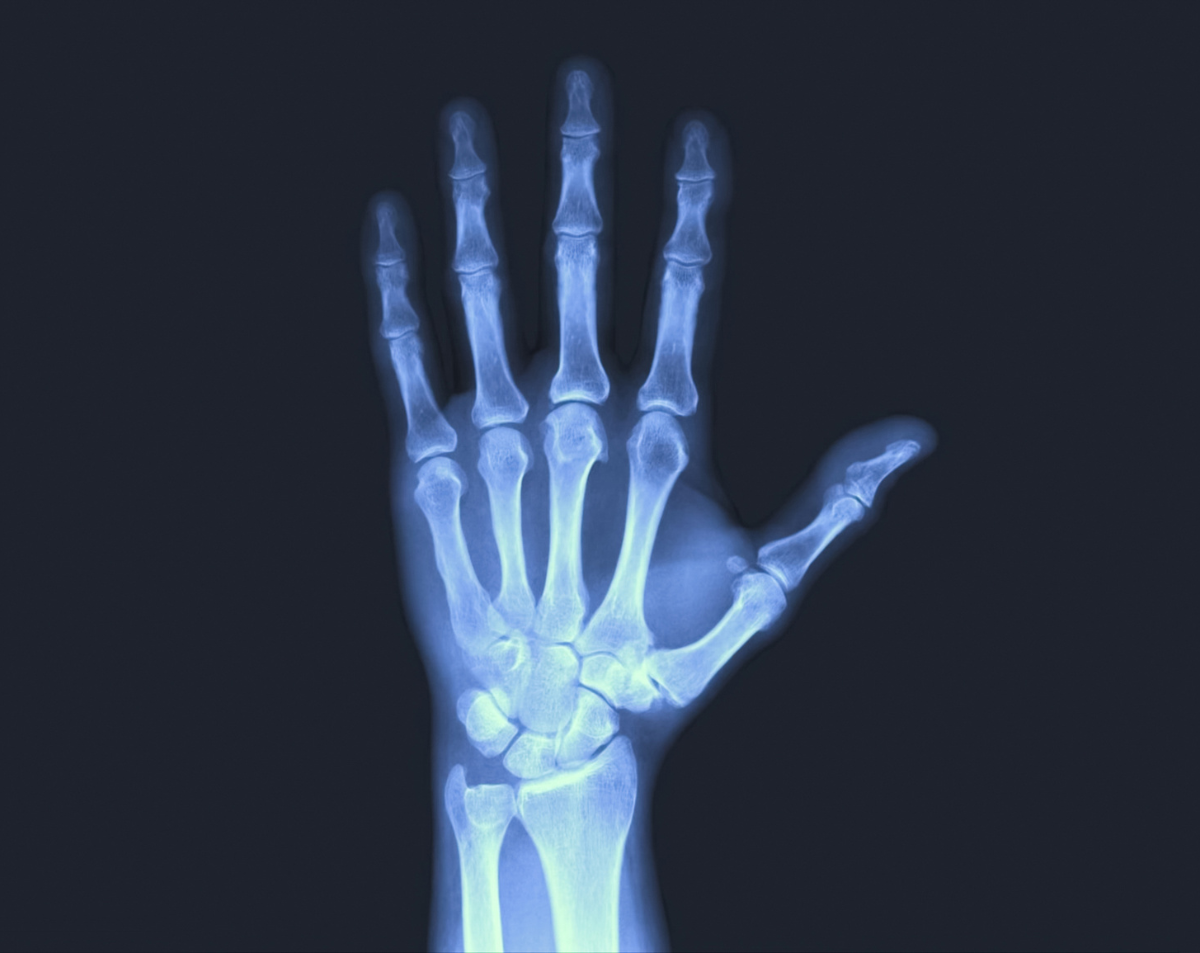

Your hands are made up of delicate bones, joints, and tissues. Because of this complexity, a hand X-ray gives your doctor crucial insight by identifying:

Fractures and breaks in the phalanges, metacarpals, or carpal bones

Joint dislocations caused by accidents or repetitive stress

Early arthritis signs like joint space narrowing or erosion

Bone infections (osteomyelitis) that cause swelling and pain

Bone tumors, cysts, or growths that need closer evaluation

Healing progress after casting, splinting, or surgery